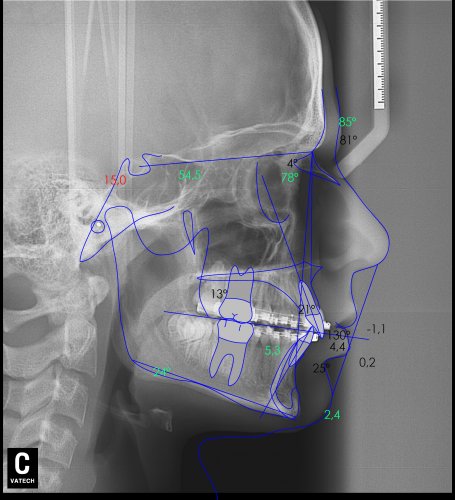

Paciente de 14 años, acude a nuestra consulta por dientes superiores proclinados hacia delante y apiñamiento. El paciente presenta una full clase 2, sobremordida y dientes inferiores proclinados. Decidimos colocarle brackets Damon y microtornillos en maxilar superior para distalizar las muelas. La duración del tratamiento fue de  24meses, y ahora lleva 1 año de contención. El paciente se pone la férula Essix superior 1noche/2 y la de abajo 1noche/semana para mantener.

Lateral Xray-2